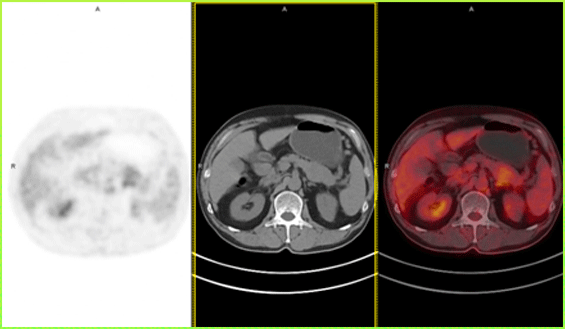

前一段时间就碰到一个七十来岁的老大爷,在当地医院体检时发现胰腺体尾部上长了个肿物,复查增强核磁、PET-CT等检查都提示恶性可能性大。

患者术前的PET-CT结果:提示胰腺体尾部稍低密度肿块影,FDG摄取异常增高